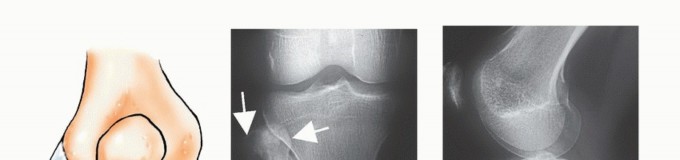

الأشعة السينية (X-rays): هي الخطوة الأولى غالبًا. توفر صورًا للعظم وتكشف عن التغيرات في بنية العظم، مثل التآكل، التصلب، أو وجود كتلة. يمكن أن تعطي مؤشرات أولية حول طبيعة الورم (حميد أو خبيث).

التصوير بالرنين المغناطيسي (MRI): يُعد MRI الأداة الأكثر قيمة لتقييم أورام العظام. يوفر صورًا مفصلة للأنسجة الرخوة المحيطة بالعظم (العضلات، الأوتار، الأعصاب، الأوعية الدموية)، ويحدد مدى انتشار الورم داخل العظم وإلى الأنسجة الرخوة المجاورة. وهو ضروري للتخطيط الجراحي للحفاظ على الطرف.

التصوير المقطعي المحوسب (CT Scan): يوفر صورًا تفصيلية لبنية العظم بدقة عالية، ويكشف عن تآكل القشرة العظمية، وتكوين العظم الجديد، وتكلسات الورم. كما يستخدم للكشف عن أي انتشار للورم إلى الرئتين (نقائل).